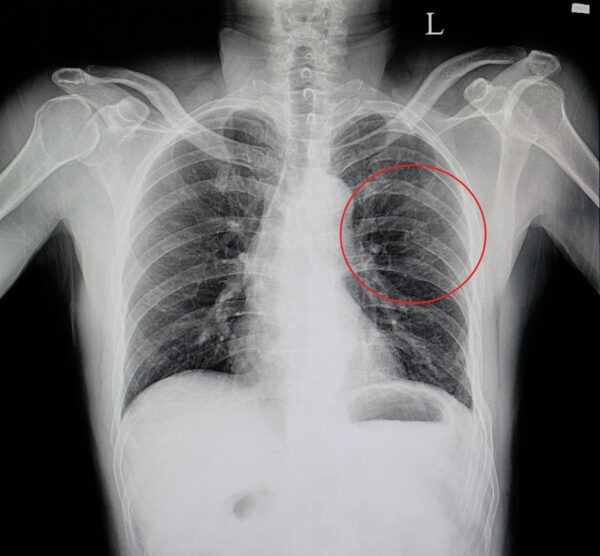

Złamanie żeber

Żebra chronią miękkie organy wewnętrzne takie jak serce czy płuca przed uszkodzeniem i urazem. Niestety, pomimo iż są one twardą tkanką kostną, mogą ulec stłuczeniu czy złamaniu na skutek urazów. Do najczęstszych przyczyn uszkodzenia żeber zaliczamy wypadki samochodowe, sporty kontaktowe czy mocne uderzenie. Żebra mogą również ulec złamaniom przeciążeniowym w trakcie wykonywania powtarzalnych czynności tj. pływanie, a także na skutek reanimacji, gdy zbyt mocny masaż serca powoduje ich uszkodzenie.

Ze względu na swoją ruchomość i czynny udział w oddychaniu, żebra nie mogą być unieruchamiane za pomocą sztywnych opatrunków gipsowych. Dlatego, w tym celu doskonale sprawdzi się nasz pas żebrowy OT-15, który delikatnie kompresuje klatkę piersiową, nie zmniejszając możliwości oddechowych pacjenta.

Żebra chronią miękkie organy wewnętrzne takie jak serce czy płuca przed uszkodzeniem i urazem. Niestety, pomimo iż są one twardą tkanką kostną, mogą ulec stłuczeniu czy złamaniu na skutek urazów. Do najczęstszych przyczyn uszkodzenia żeber zaliczamy wypadki samochodowe, sporty kontaktowe czy mocne uderzenie. Żebra mogą również ulec złamaniom przeciążeniowym w trakcie wykonywania powtarzalnych czynności tj. pływanie, a także na skutek reanimacji, gdy zbyt mocny masaż serca powoduje ich uszkodzenie.

Ze względu na swoją ruchomość i czynny udział w oddychaniu, żebra nie mogą być unieruchamiane za pomocą sztywnych opatrunków gipsowych. Dlatego, w tym celu doskonale sprawdzi się nasz pas żebrowy OT-15, który delikatnie kompresuje klatkę piersiową, nie zmniejszając możliwości oddechowych pacjenta.